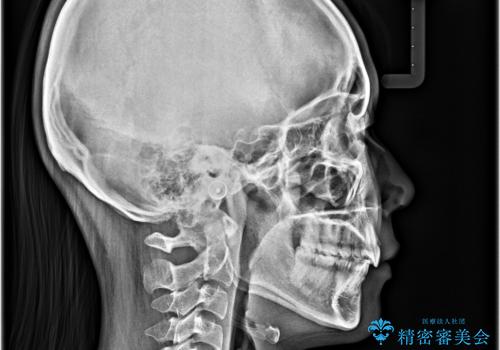

骨格的な出っ歯を抜歯矯正で改善 横顔の印象が劇的に変化

- 飛び出した上顎前歯と、閉じにくい唇、口元の突出した印象の横顔を気にして来院された患者様です。

骨格的な上顎前突であり、上下前歯の前後的な距離が大きいため、上顎は左右第一小臼歯を、下顎は左右第二小臼歯をそれぞれ2本抜歯することで前歯が接触するようにし、さらには奥歯の咬み合わせも、より理想的な状態へ近づけていくこととしました。

3年以上はかかる難症例であるため、表側のワイヤー装置にて治療を行うこととしました。

事前の予想通り、長期間を要する治療となりましたが、横顔の印象が劇的に変化し、患者様には大変満足していただきました。